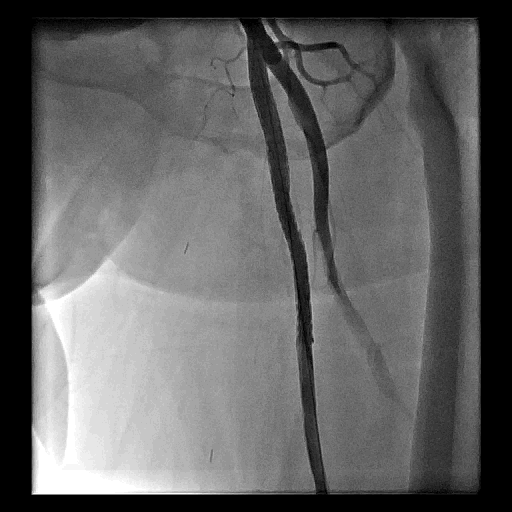

Figure 1. 淺股動脈的使用經皮腔內血管成形術治療

C. 血管支架置放

D. 打通右側淺股動脈